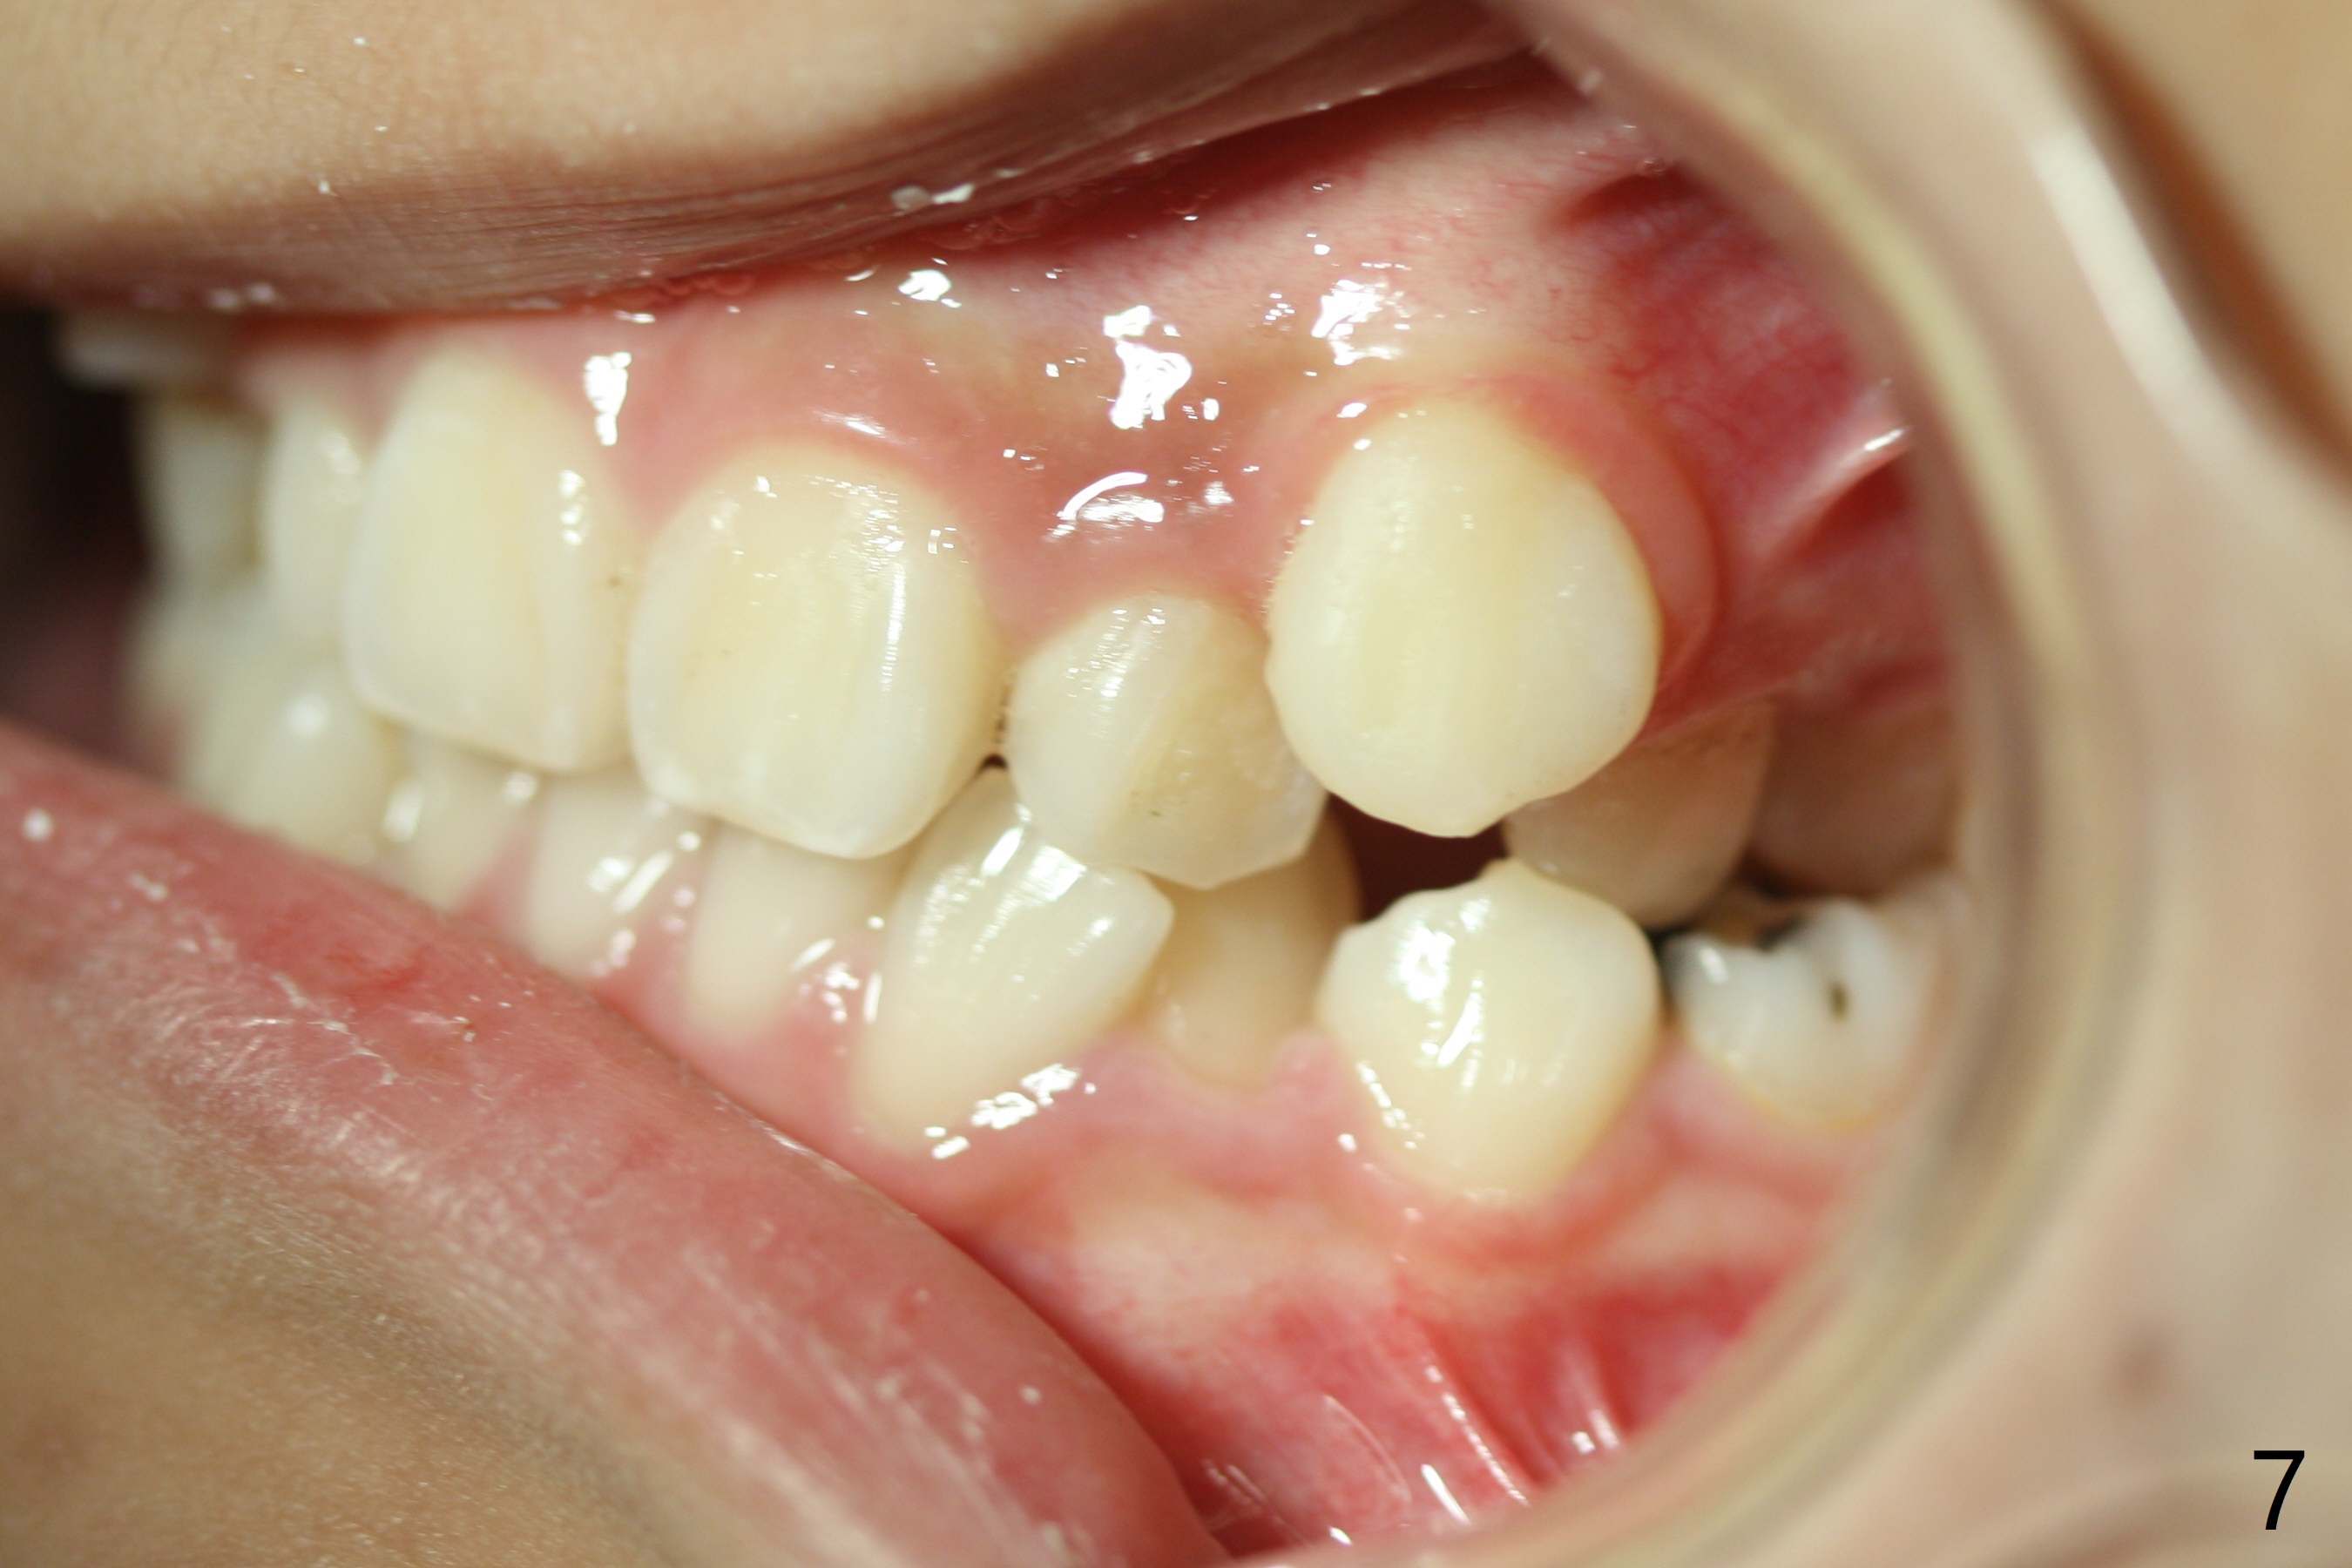

Severe crowding with normal facial profile appears to dictate extraction of 4 bicuspids and of the lower 2nd primary molars (Fig.1-11).  Since there is no time for banding before school, delay in orthodontic treatment post extraction will lose space?

Dear Dr. Shaughnessy: can you open the following link?  I would like to try to extract 4 bicuspids and 2 lower primary 2nd molars and let the canines shift by themselves.  But I wonder whether the 2nd permanent bicuspids, especially the upper ones, may shift mesially instead.  How would you like to handle the situation?

If you are concerned with losing space in the U arch post-extraction, you could always place a space maintainer.  I am not concerned in the lower arch.

Or, if you place brackets you can add a stop in the arch wire at the U6 to prevent mesial migration.

Sometimes I do not bracket the canines immediately.  I allow them to erupt a bit or tease them down with buttons then bracket them-so that the AW is less deflected.  A NiTi arch wire can be deflected a lot but sometimes I do not want to do that for fear I will see reciprocal side effects that I do not want!  Tim